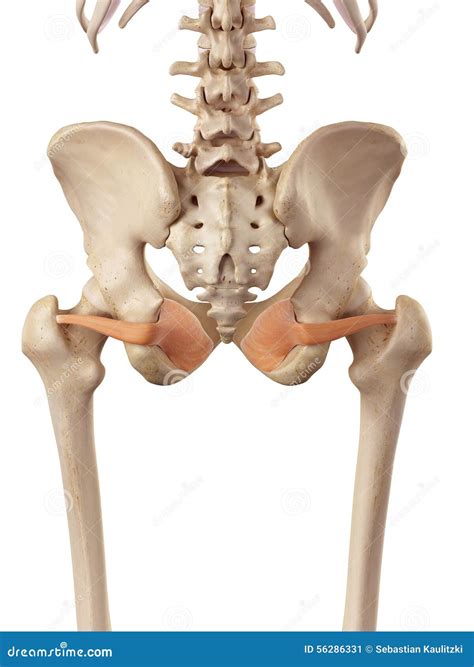

Anatomical representation of the hip region

The Obturator Externus Muscle is situated in the upper portion of the medial thigh. It is a flat, triangular muscle that originates from the external surface of the obturator membrane and the surrounding bony margins of the obturator foramen. From this origin, the fibers pass laterally, wrapping around the neck of the femur, and insert into the trochanteric fossa of the femur.

Because of its deep positioning, it is covered by several larger muscles, including the adductor magnus and the pectineus. Its proximity to the hip joint capsule makes it an intimate stabilizer, helping to keep the femoral head securely seated within the acetabulum (the hip socket). Anatomically, it belongs to the lateral rotator group of the hip, working in synergy with the piriformis, gemelli, and quadratus femoris.